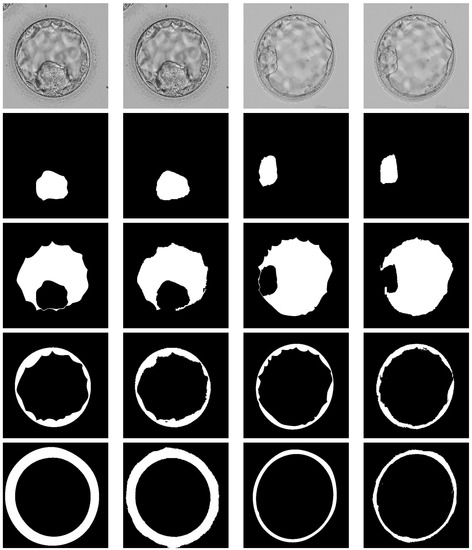

4.1. Dataset and Augmentation